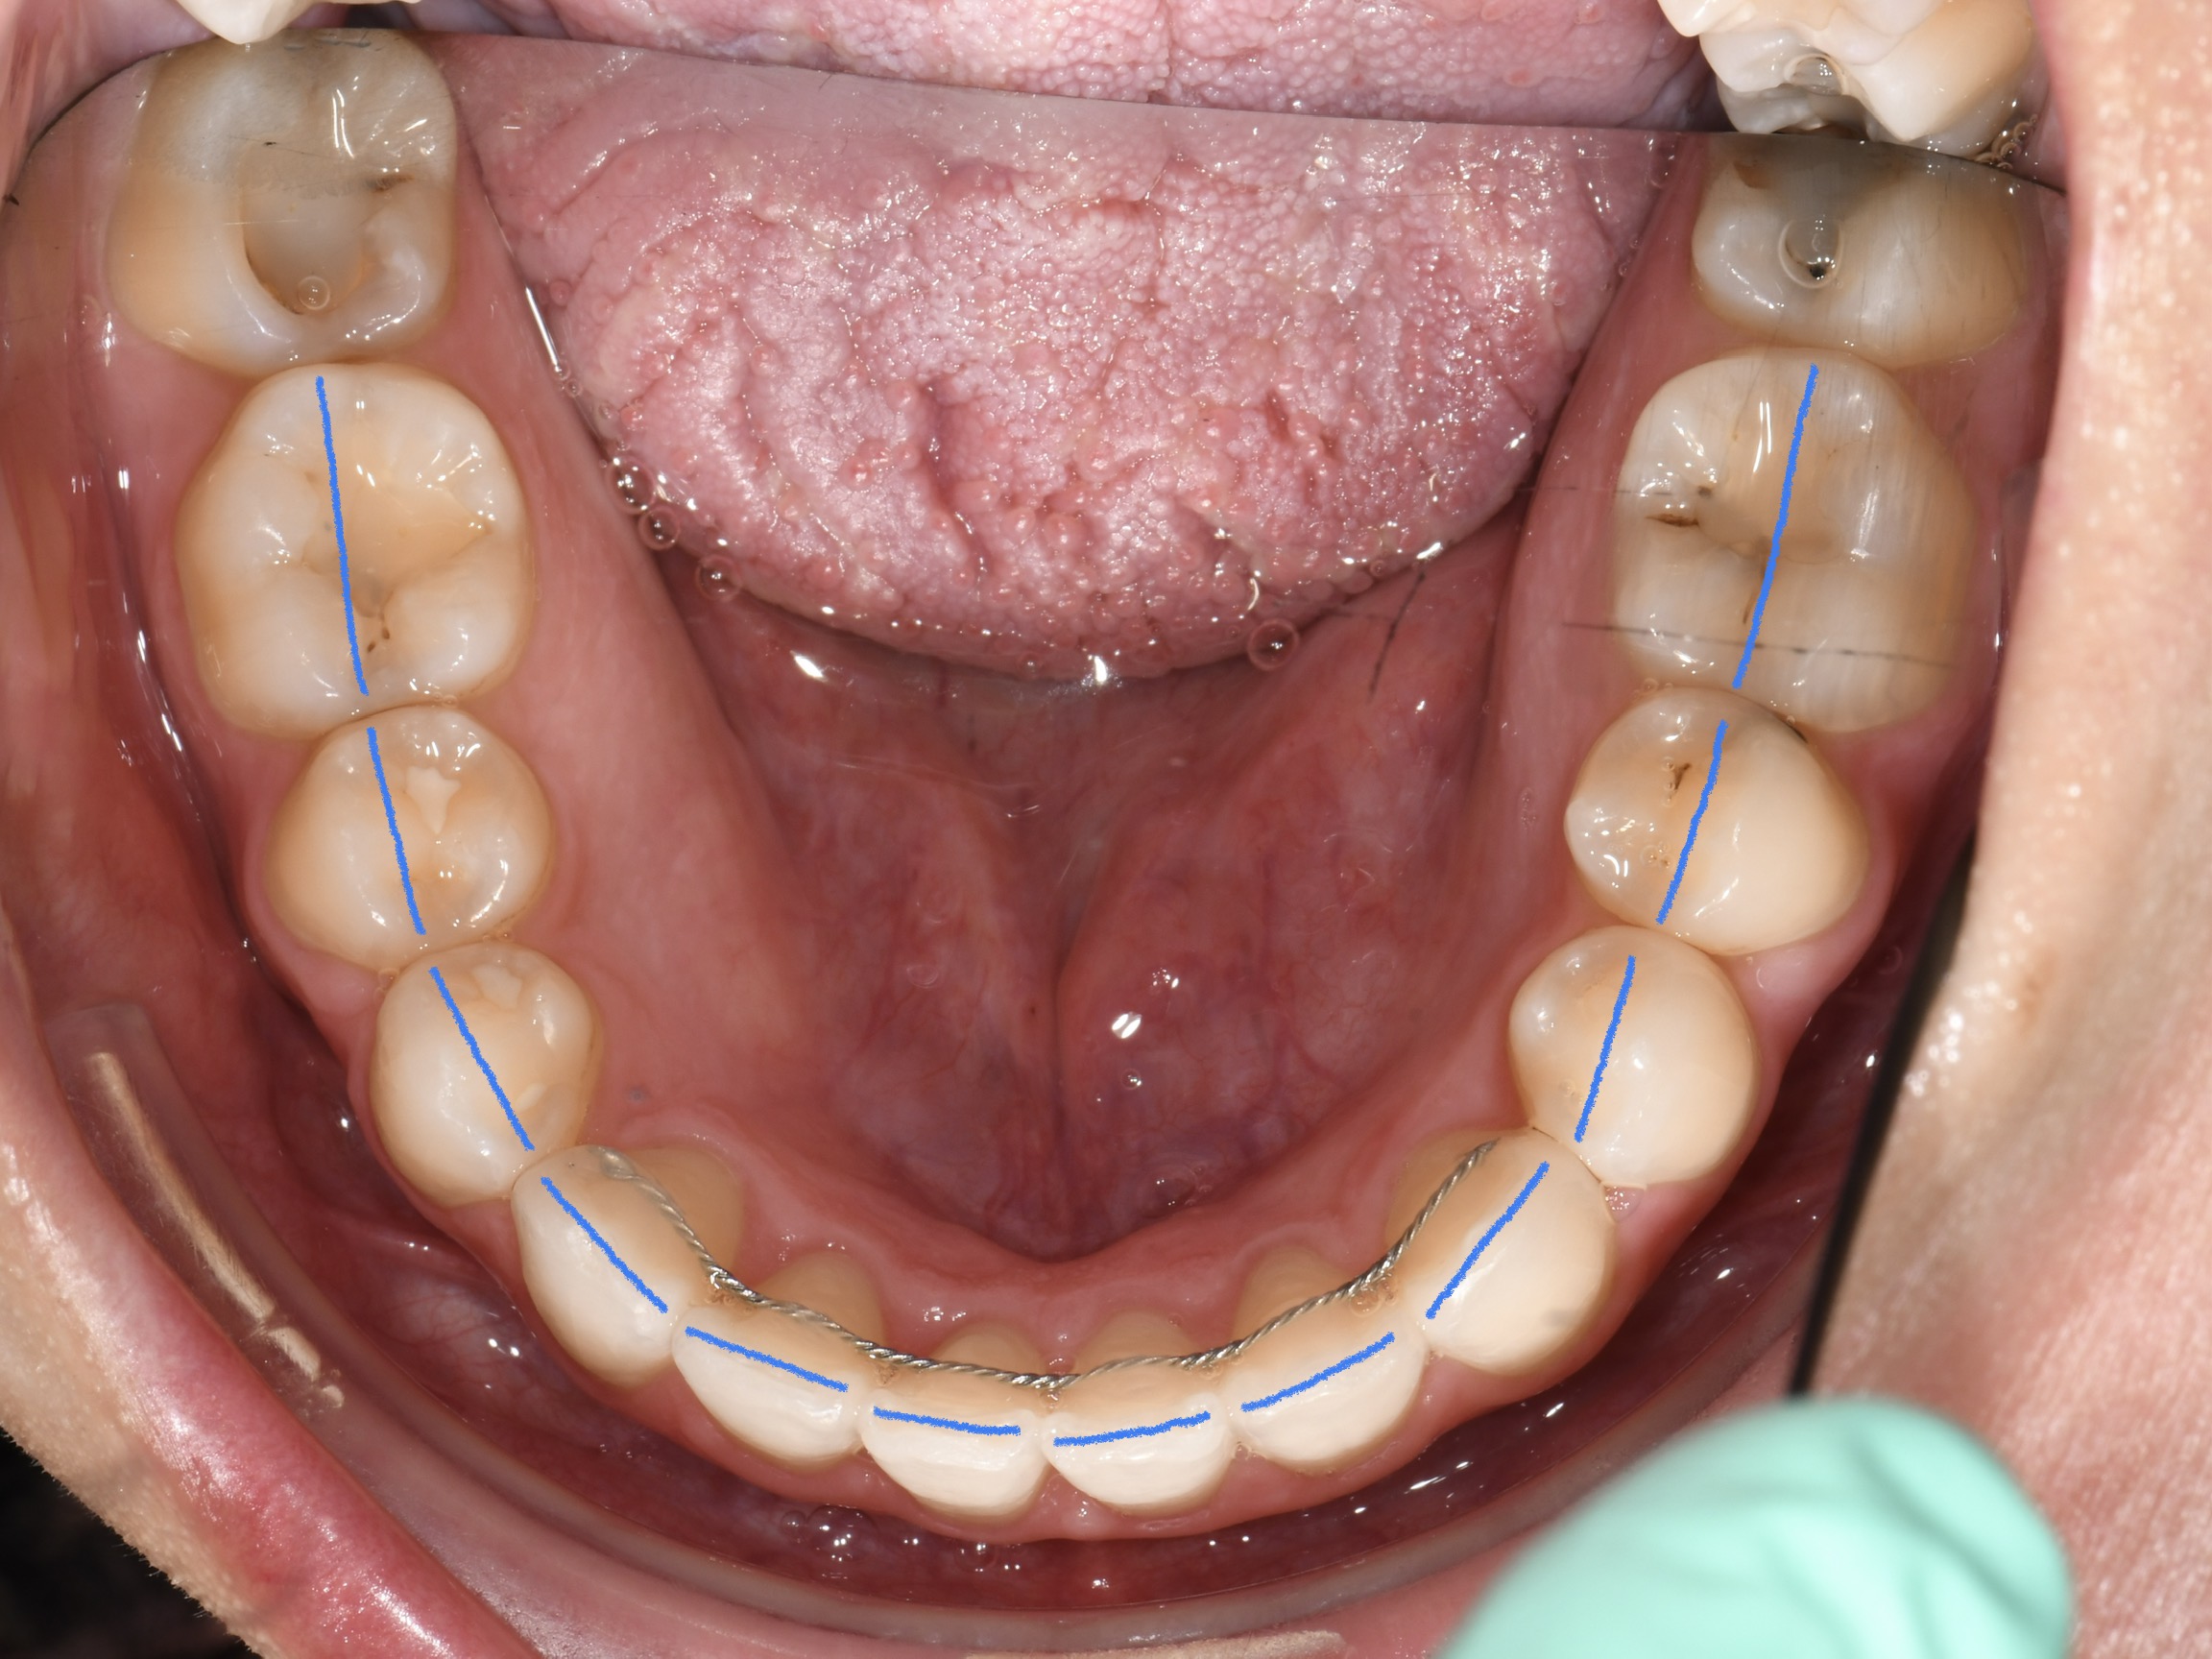

Az elmúlt évekből rengeteg szakmai referenciát tudnánk bemutatni, amelyek különböző fogszabályozási problémákat oldottak meg. Válogatva a több száz esetből, ezen az oldalon olyan képeket, információkat igyekeztünk bemutatni, amelyeknek a segítségével a jövőbeni pácienseinknek azt tudjuk üzenni: A Te fogsorod is lehet gyönyörű!

(Képeket a Pácienseink külön írásos beleegyezésével mutatjuk be!)